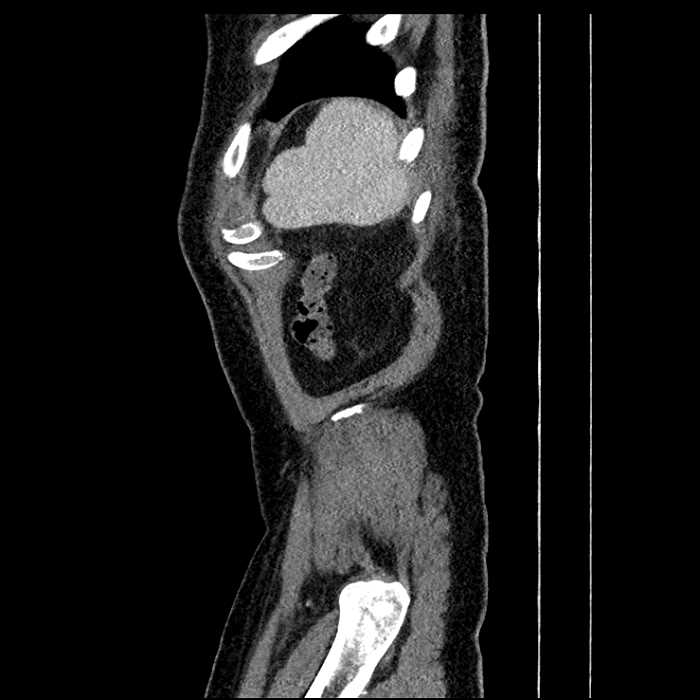

• Large fluid density structure in hepatic segments 7 and 8 measuring 10 x 7 x 7 cm with internal septation and circumferential ill-defined low density compatible with edema

• Peripherally enhancing subcapsular collections along the anterior margin of the left hepatic lobe measuring 3 x 1 cm and 2 x 1 cm

• Clearly marginated fluid density structure in segment 7 and several other scattered tiny hypodensities, which likely represent cysts

• Hepatic abscess

Acute sigmoid diverticulitis complicated by a small contained perforation and a large abscess in the right hepatic lobe. Additional small subcapsular abscesses along the anterior margin of the left hepatic lobe.

• The classic CT imaging appearance is a double target sign with internal low density surrounded by an internal enhancing rim (capsule) and a low density external rim (edema)

• Abscesses may be unilocular or multilocular

Hepatic abscess showing the double target sign with low density internally surrounded by a thin inner enhancing rim (red arrow) and ill-defined outer low density rim (yellow arrow). Blue arrow indicates an internal septation. Red arrows: additional smaller subcapsular abscesses. Red arrow: focal contained perforation associated with diverticulitis.